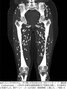

【Photo】生焼けの豚肉で寄生虫に感染…「嚢虫症」患者の脚のCT写真

ガリ博士が公開した患者のCT写真でも、大腿(だいたい)骨や膝関節の下などに広がる白い楕円形の嚢胞が確認できる。

これはレントゲン撮影で白い楕円(だえん)形の米粒のような形で現れる。

体内に入り込んだ幼虫は5-12週ほどで胃や腸の中で成虫となり、身体の他の組織などに移動する。皮膚の下に固まりの存在を感じる石灰化した嚢胞や病変が形成される。